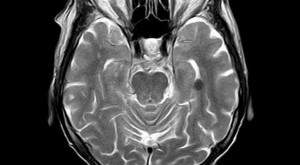

This is the physiological state that occurs during prayer. It involves the autonomic (automatic) nervous system shifting over to a parasympathetic (rest and digest) dominant state, as opposed to the sympathetic (fight, flight, freeze) state that most of us spend the majority of the day in. The act of prayer has shown to increase certain helpful neurotransmitters, such as dopamine, which help promote a state of relaxation, focus, motivation, and well-being. But the effects are not confined to momentary relaxation. Long-term prayer can actually rewire and rebuild the brain! With the ability to scan the brain using magnetic resonance imaging (MRI), researchers have been able to note the physiological changes that occur in the brains of those who pray regularly.

Lisa Miller, professor and director of Clinical Psychology and director of the Spirituality Mind Body Institute at Teachers College, Columbia University conducted a study on 103 people who were at a high risk of depression. Using MRI, she found that those who prayed regularly tended to have a thicker cerebral cortex which has been associated with less depression and anxiety. Another study has shown that urban children with asthma cope better when incorporating prayer into their lives. Prayer is also good for your heart. Christians have been shown to have lower average blood-pressure than non-believers. Prayer also is correlated to less heart attacks and quicker recovery from heart surgery. There is even evidence to suggest that regular prayer will help you live longer! So with all these benefits, you should consider incorporating prayer as part of your daily regimen.

Ken Gorman suffered excruciating pain after a small lump, discovered at the end of May 2013, grew bigger and bigger. Doctors prescribed tablets for the pain and sent him to Rotherham General Hospital for investigation, where an MRI scan found three tumors (or three broken sections of a tumor) wrapped around the central nerve in the side of his face.